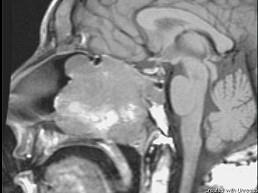

15岁,男性,渐进性鼻塞1年余,MRI扫描如图所示,请选择最可能诊断 ( )

• A.鼻咽部脓肿

• B.鼻咽部纤维血管瘤

• C.脊索瘤

• D.鼻咽癌

• E.鼻咽部囊肿

答案: B